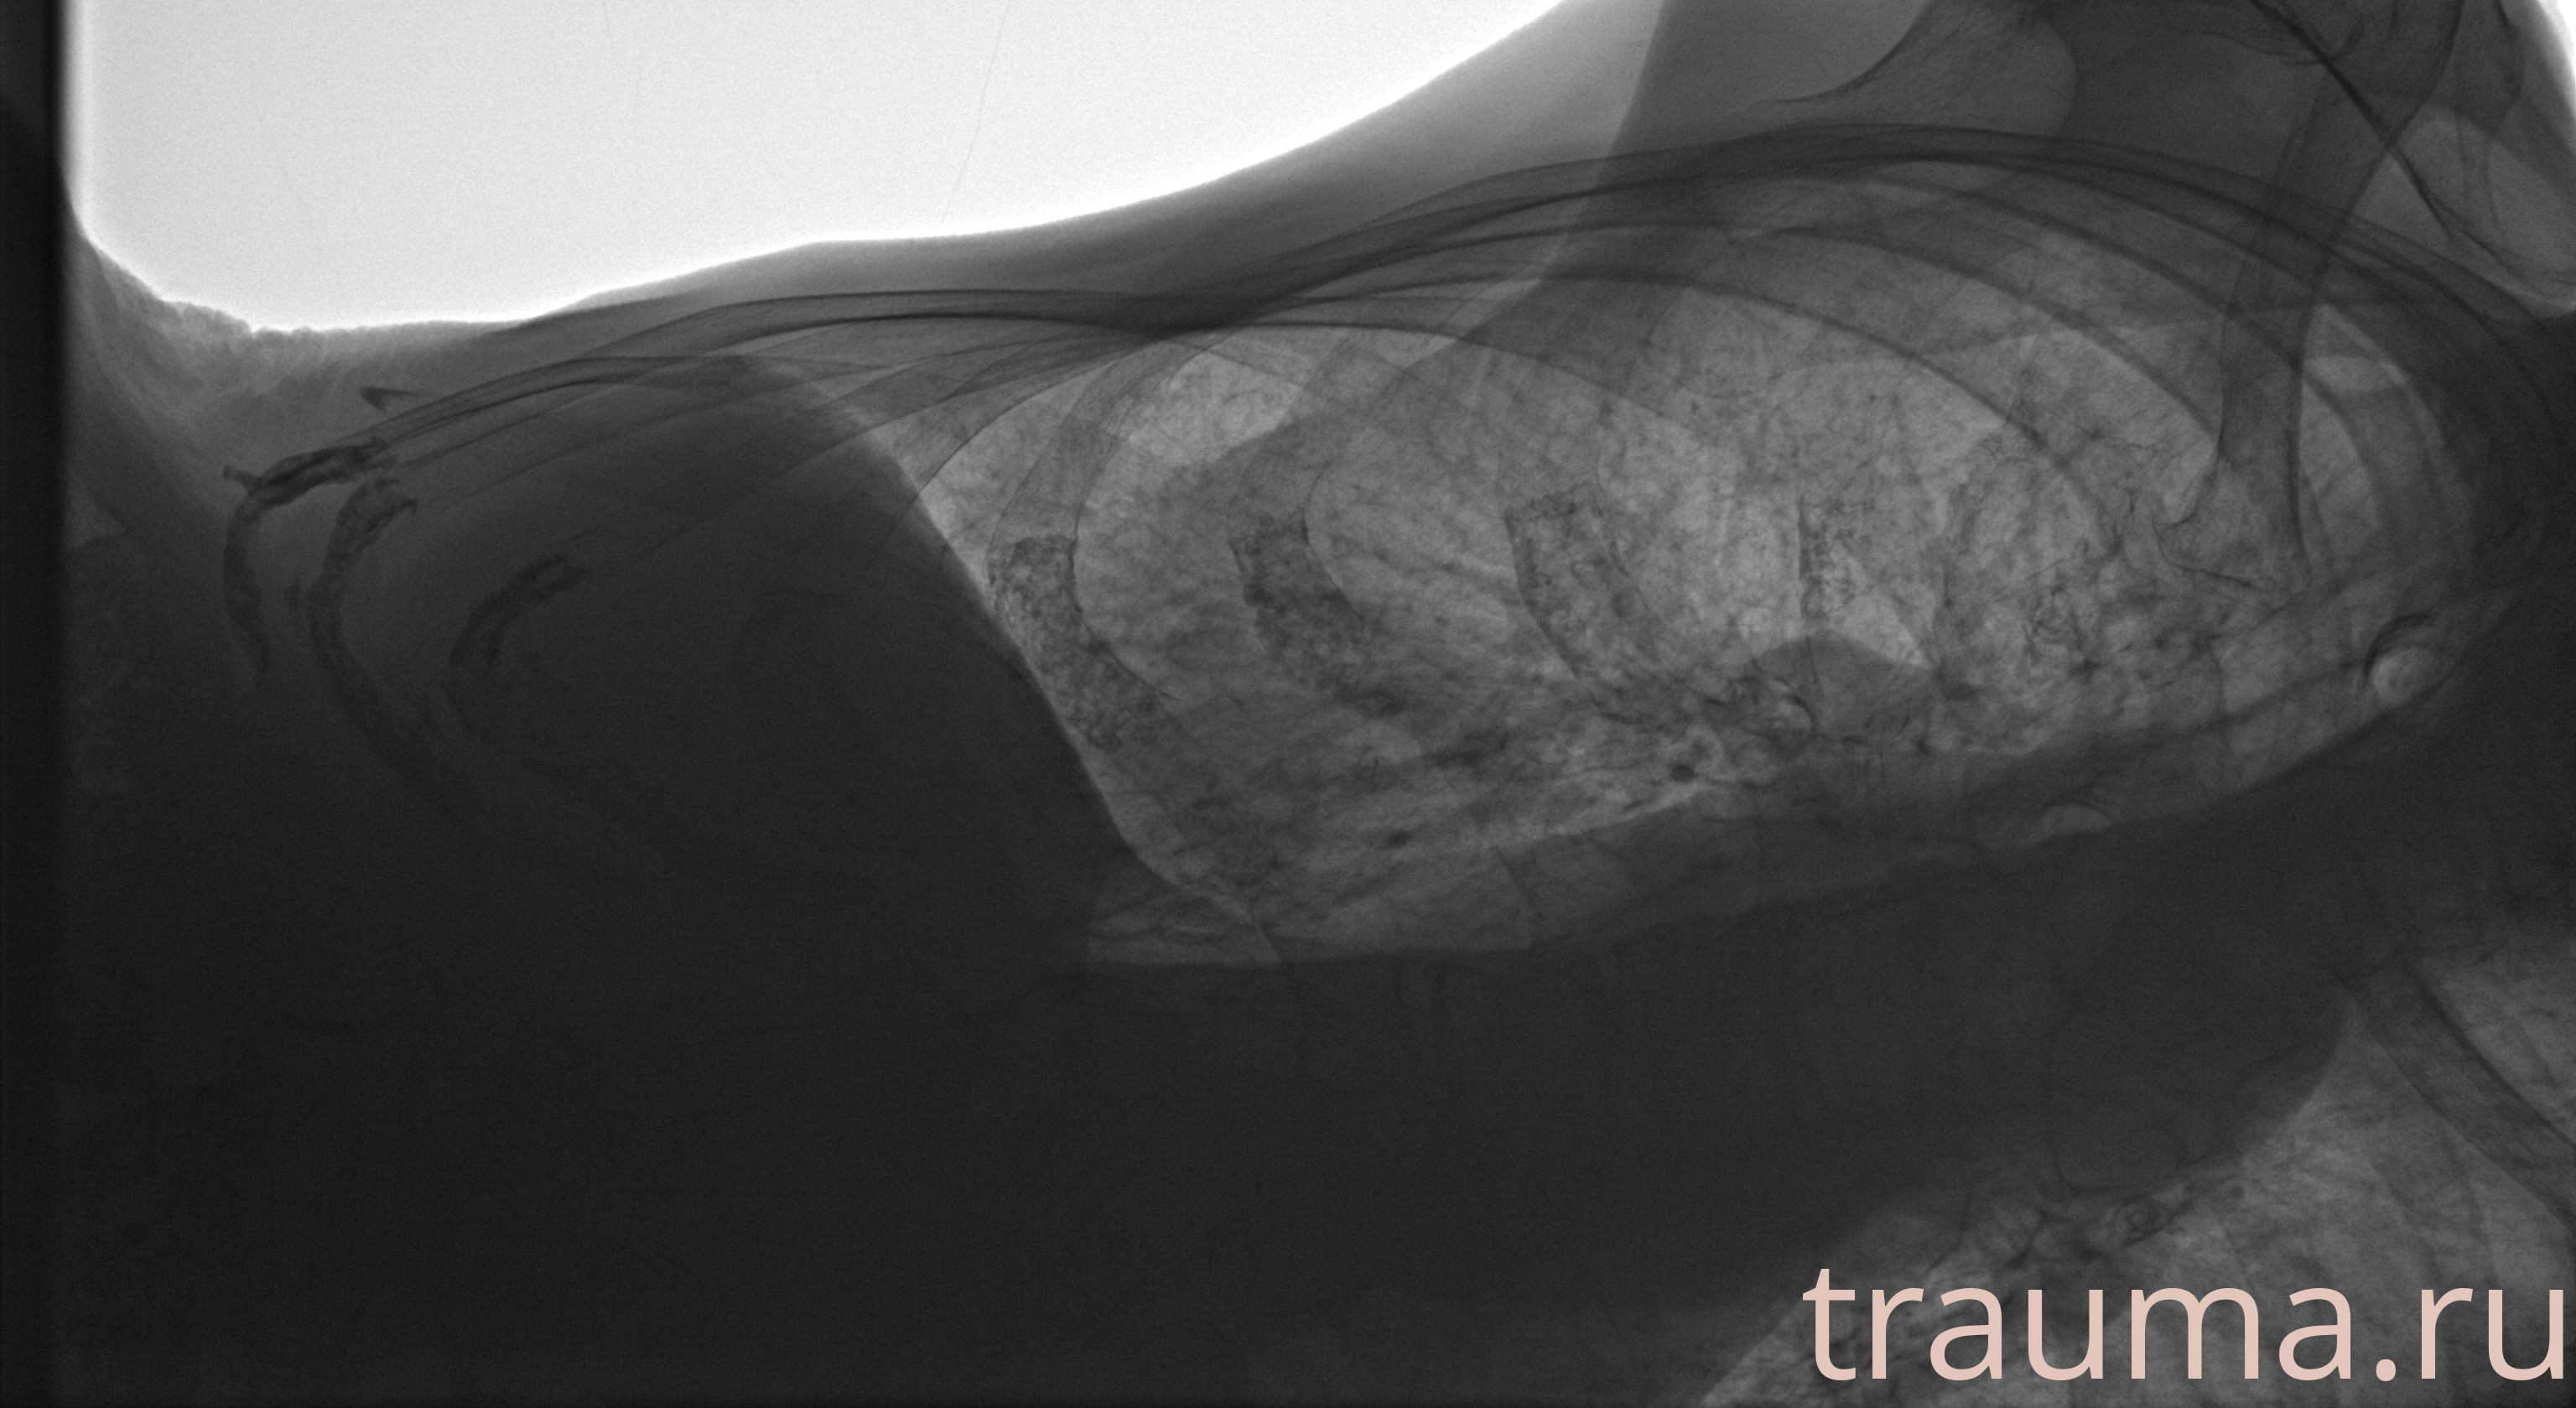

Рентгенограммы

Рентген на дому: по вашему адресу приезжает врач-рентгенолог, травматолог-ортопед с мобильным рентгеновским аппаратом, проводит диагностику травмы или заболевания, делает необходимые рентгенограммы, дает рекомендации по дальнейшему лечению. Получить качественные снимки в домашних условиях возможно благодаря уникальной методике, разработанной МосРентген Центром для института  Склифосовского